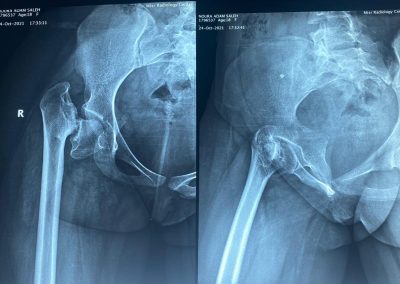

أشعة لمفصل الحوض تبين كسر قديم مهمل كما تبين وجود قصر شديد بالطرف السفلي.